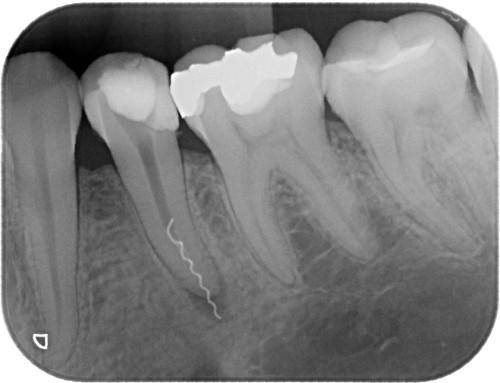

Была проведена эндодонтическая подготовка зубов, все корневые каналы были вылечены, запломбированы и прикрыты временными пломбами.

Каждые два месяца проводился контроль при помощи телерентгенограммы височно-нижнечелюстного сустава. В итоге высота прикуса при помощи использования пластичных протезов увеличилась. В течение этого времени проводилась их регулярная перебазировка. Разобщение верхнего и нижнего зубных рядов становилось больше.

После появления необходимой высоты прикуса на передние зубы были изготовлены и установлены пластмассовые корневые вкладки и на них выполнены временные коронки.

Изготовление металлических вкладок пока было преждевременно, так как можно было ошибиться с размером и наклоном в переднезаднем направлении. С появлением временных пластмассовых коронок пациент стал улыбаться, смог не только пережевывать, но и откусывать пищу передними зубами. Так как изменение высоты прикуса происходило постепенно, пациент быстро и благополучно привыкал к создавшемуся положению и явлений дискомфорта не испытывал.